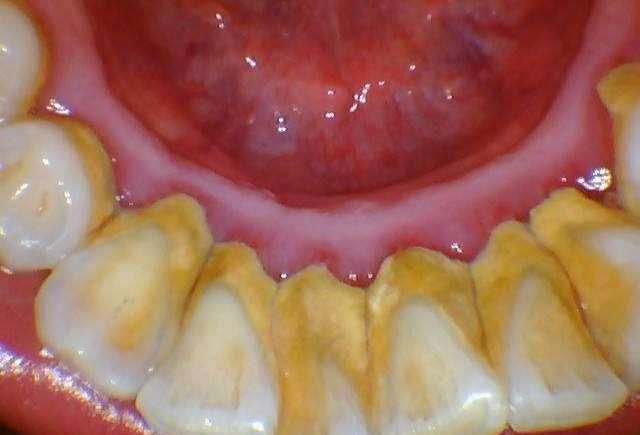

2.牙结石

牙结石是指长期沉积在牙齿上矿化的菌斑,牙结石对牙周组织的危害,主要是构成了菌斑附着同时也是细菌滋生提供了良好生存环境,长期牙结石不清理会产生严重的牙周炎。